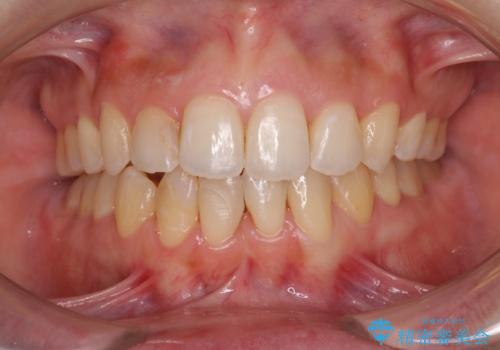

下顎前歯と上顎の部分矯正

- 上下の前歯の叢生を気にして来院された患者様です。

前歯のみの矯正治療を希望でしたが、上顎臼歯が舌側転位していたため、上顎は全体を、下顎は前歯のみを矯正治療することとしました。

矯正治療は上下全顎を行うことが大前提ですが、費用などの点から、今回は部分矯正を選択することとなりました。

患者様本人は咬みにくさを感じていないようですが、部分矯正は咬み合わせの改善が困難であることが多く、咬みにくさが残ることがあります。